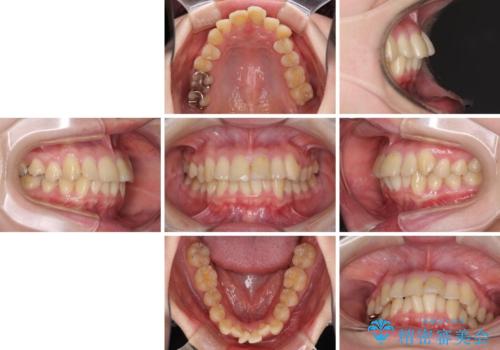

上下前歯のデコボコをきれいに インビザラインによる矯正治療

- 前歯の著しい叢生と前突感を気にして来院された患者様です。

叢生が強いため、事前に前歯をワイヤー矯正で速やかに叢生を解消し、その後はインビザラインにて矯正治療を行うこととしました。

ワイヤー矯正を併用したことで前歯の叢生を速やかに解消することができました。

一方口元の突出感を改善するために時間がかかり、2年超を要しましたが、満足のいく仕上がりとなりました。